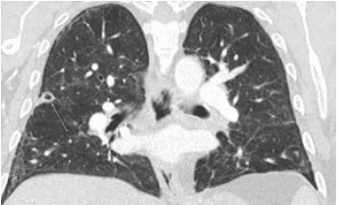

66 year old male with a history of a kidney transplant presented with progressive painful plaque-like lesions on his distal finger and toe. CT angiogram revealed pulmonary nodules with cavitation. Broad-spectrum antimicrobial therapy was started.

"Computer tomography (CT) coronal view of right upper lobe cavitary lesion with several bilateral pulmonary nodules seen"